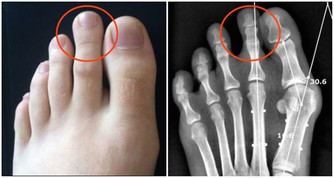

痛風,幾乎也是讓大家聞之色變的一類疾病了,因為一旦患上了痛風,不僅身體會長時間受到折磨,精神上也會感到十分痛苦,而且在痛風患者的日常生活中,稍有不慎就可能會導致其他病症一齊發作。